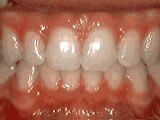

Patient sucked her thumb as a young child. She started treatment at age 13. She had braces and a special appliance — called a crib — to retrain the tongue, for 28 months. Now she can bite the lettuce out of a sandwich.